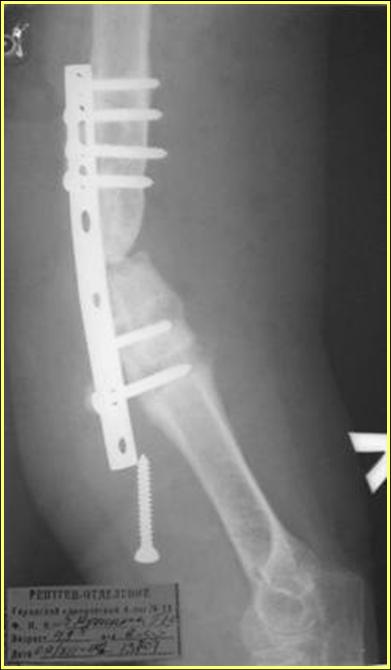

> Уважаемые коллеги! Обратилась женщина 38 лет, соматически здорова,

> ORIF наружным доступом в 2005 году (к сожалению

> снимки пока не нашли), перелом типа В1. После остеосинтеза никуда

> не обращалась. Летом прошлого года (через 2 года

> после операции) во время перетаскивания стиральной машины появились

> боли в оперированном плече, но пришла лишь

> сейчас. Клинически: варусная деформация, патологическая

> подвижность, объем движений в локтевом суставе почти полный,

> неврологических расстройств нет, признаков инфекции нет. Коллеги,

> как вы думаете, возможно ли срастить данный

> неоартроз? Микрохирургия  недоступна. Честно говоря, не встречаясь

> с такими последствиями никогда ранее, надеюсь на

> помощь "коллективного разума".

Типичная положительная ситуация для интрамедуллярного остеосинтеза с

использованием опорного металлокаркаса для компенсации дефекта.

Послеоперационное ведение активное или агрессивно-активное.  Каркасы

можно заказать в МАТИ. Успехов. ЛАФ.